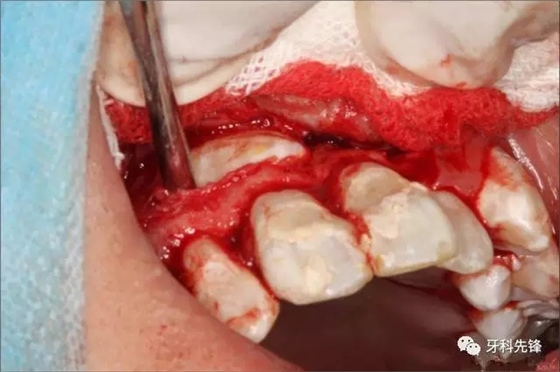

圖5.局麻下行唇側梯形切口

圖6.翻瓣、去骨、暴露13牙冠